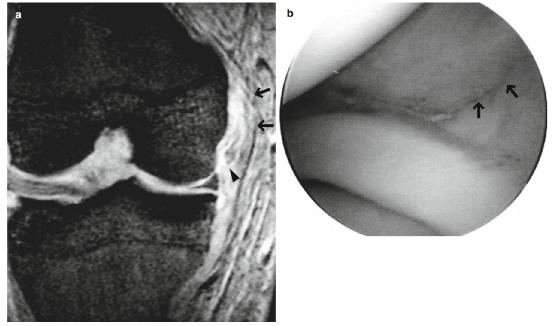

在2-3级MCL撕裂中,将会看到由于水肿和血肿导致的纤维不连续和信号异常(图5.8和5.9)。

- 除非MCL的深层被破坏,否则关节镜检查不会发现任何病理结果(图5.9b)。

图5.9 3级撕裂(完全撕裂)。一个十八九岁的男性。(a)冠状T2*WI和(b)关节镜图像显示MCL近端部分完全撕裂(箭头),周围有水肿改变。在(b)中,关节囊的破裂(MCL的深层,箭头)可见。注意撕裂的半月板股韧带(MCL深层,a中箭头所示)